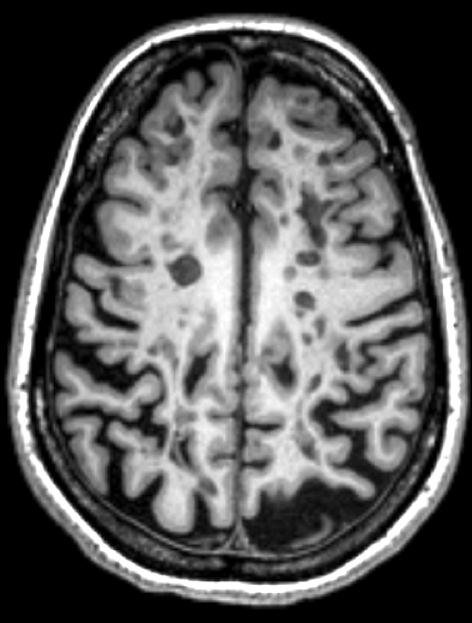

Mindcontrol

A dashboard for collaborative brain quality control and annotation

A fruitful collaboration @ UCSF

Now, as postdoc:

studying

Mental Health

-

Public dataset, 10k images

Motion → bad quality images

Visual inspection before & during analysis

Too time consuming in the “wet lab”